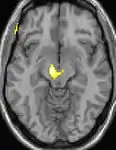

As reais causas da cefaleia em salvas (CES) ainda são desconhecidas, mas, de acordo com alguns estudos, os padrões das crises, as influências pelo horário do dia e as estações sugerem que o relógio biológico do corpo está envolvido. Nos seres humanos, o relógio biológico está situado no hipotálamo. Durante um ataque, o hipotálamo libera substâncias químicas que podem estimular as células nervosas no cérebro, causando dor e outros sintomas. A hiperatividade nervosa também pode causar um alargamento (vasodilatação) das artérias no lado afetado do cérebro. Uma teoria é que as dores são causadas por um alargamento dos vasos sanguíneos, que pressionam sobre os tecidos nervosos próximos, causando dor.[4] Exames de ressonância magnética sugerem dilatação da artéria oftálmica durante uma crise de cefaleia, enquanto a tomografia por emissão de pósitrons (PET) revela atividade dentro do seio cavernoso. Em alguns casos, existem fatores genéticos também, pois é mais comum entre familiares.[5]

| Tomografia PET mostrando áreas ativadas na dor. | ||

| VBM mostrando diferenças estruturais entre cérebros | ||